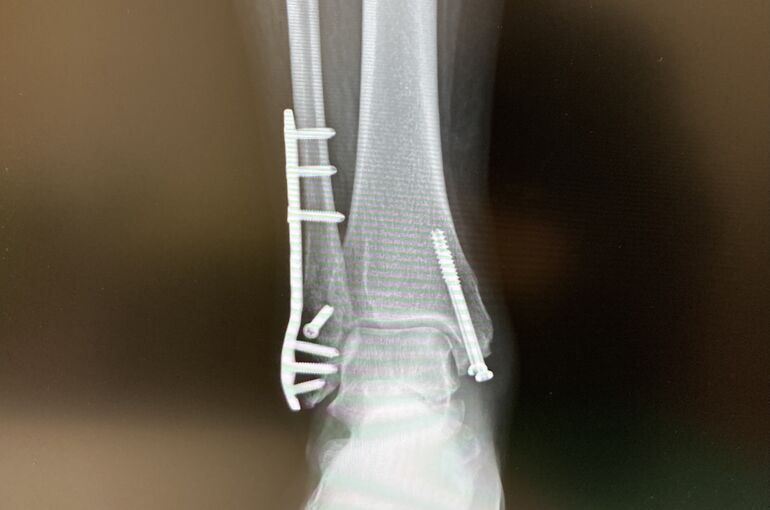

1枚目の写真、プレートとボルトを取り除いた、エックス線(レントゲン)写真。

骨のところに、はっきりとボルトの後が、残っているのがわかります。